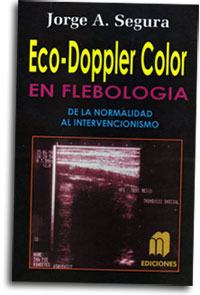

- Autor de los libros: “Ecodoppler color en flebología, de la normalidad al intervencionismo” (2011) y “Manual de flebopatías superficiales” (2015).